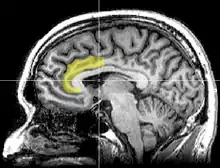

Corte MRI sagital con indicación de la ubicación del córtex del cíngulo anterior.